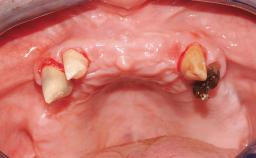

This case features the flapless computer-guided placement of 7 bone-level implants, distributed to provide maximal support for the prosthetic framework. A rigid one-piece metallic framework was utilized as an interim restoration to reduce the risk of fracture associated with this prosthetic design. As part of the clinical examination, the SAC Assessment Tool was used, resulting in a surgical and restorative risk classification as “complex”.